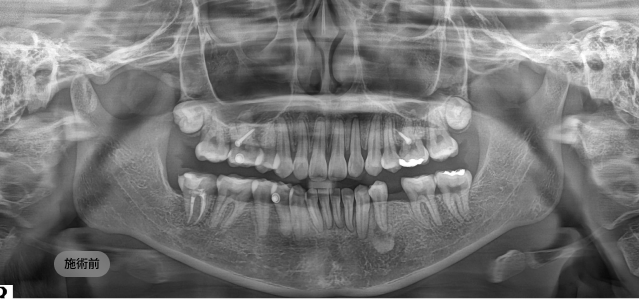

画面をドラッグして前/後を比較してみてください